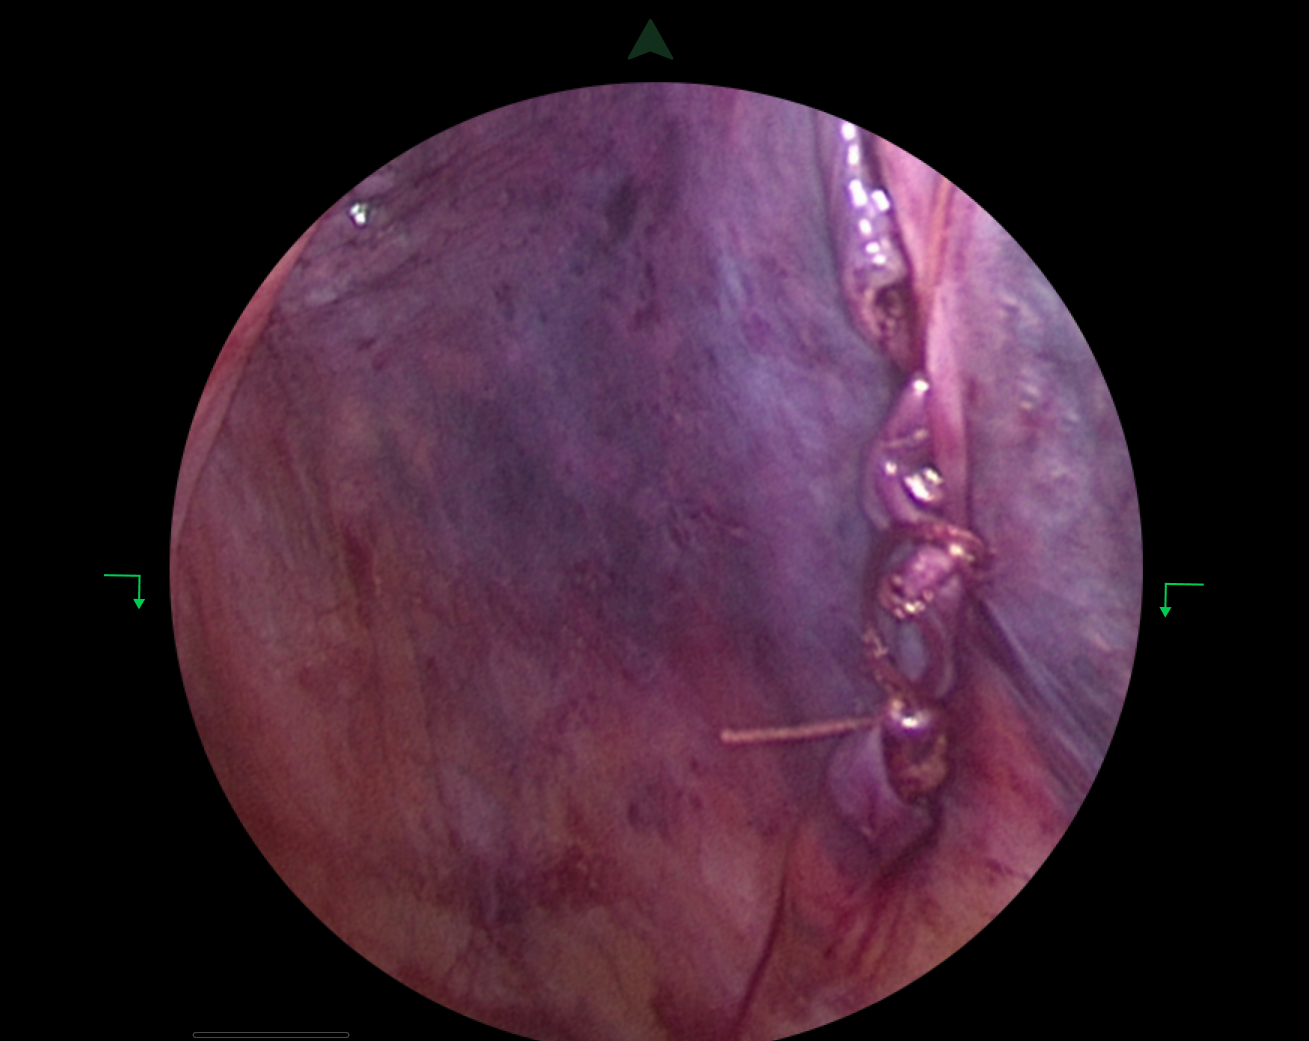

The Journey in Pictures

From initial sketches to final prototypes – see how I brought this vision to life

Surgeons tested prototypes in actual operating rooms

- Tested prototypes in real operating room environments

- Collected feedback from surgeons during actual procedures